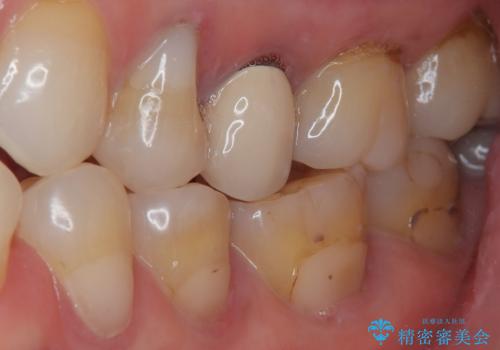

相談の上、フルジルコニアクラウンにて補綴治療を行うこととしました。

仮歯装着によりしみていた症状はおさまり、無事に治療を終えることができました。